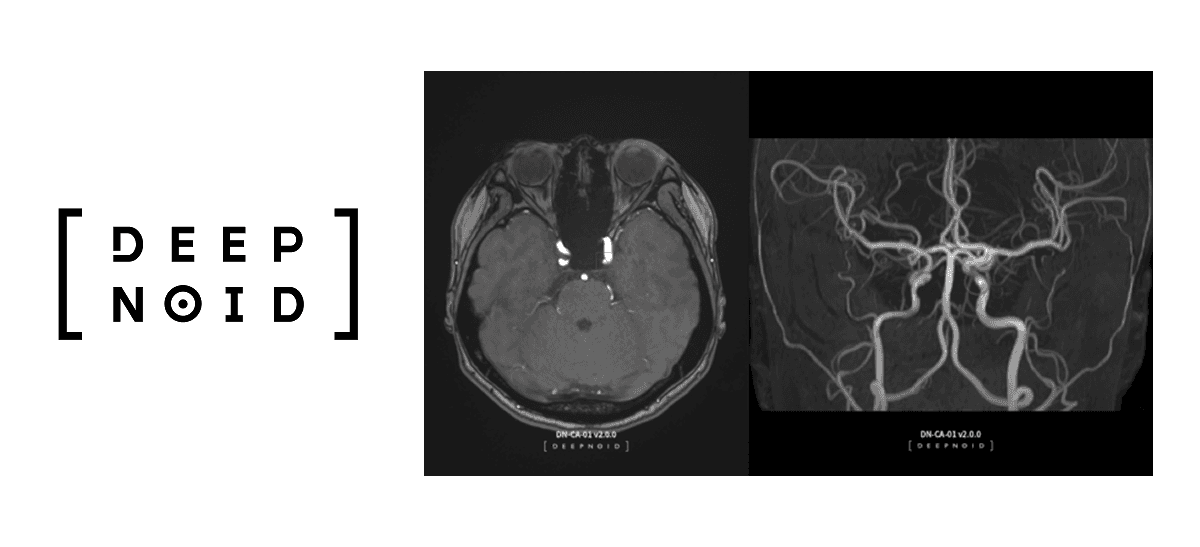

딥노이드는 다양한 의료 AI 솔루션을 제공하는 기업입니다.

대표적인 솔루션으로는 DEEP AI 시리즈가 있습니다.

딥뉴로: 뇌 MRA 의료 영상 판독 보조 솔루션으로, 뇌 질환을 신속하고 정확하게 진단할 수 있습니다.